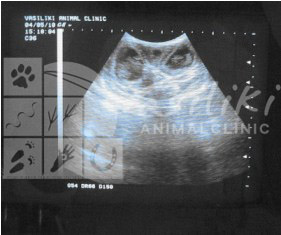

Ήρθε για πρώτη φορά στο ιατρείο στα μέσα Απριλίου όπου και διαπιστώθηκε ,μετά από εξέταση με υπέρηχο, η εγκυμοσύνη της. Η Ήρα κυοφορούσε δύο έμβρυα.

Η Ήρα ήρθε στο ιατρείο δύο ακόμα φορές κατά την διάρκεια της εγκυμοσύνης της για έλεγχο και εξέταση με υπέρηχο προκειμένου να διαπιστωθεί η ομαλή ανάπτυξη και υγεία των εμβρύων της.